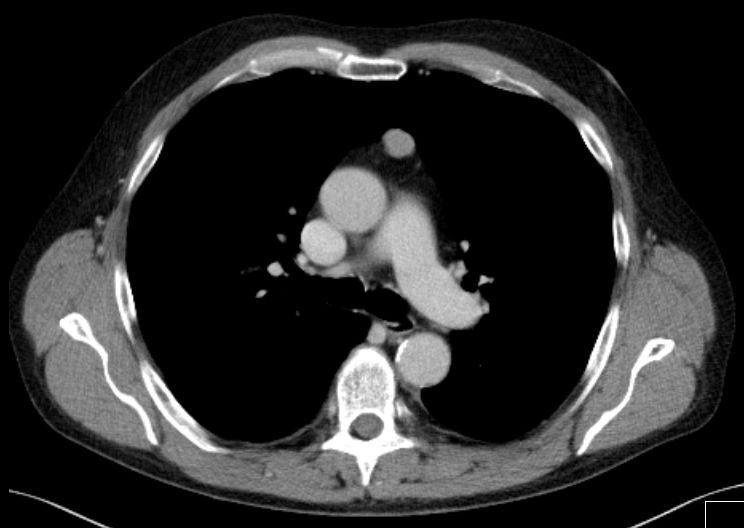

| Metastasierung | 65-jähriger Mann mit primär metastasiertem Merkelzelltumor.

Metastase im vorderen Mediastinum![]() |